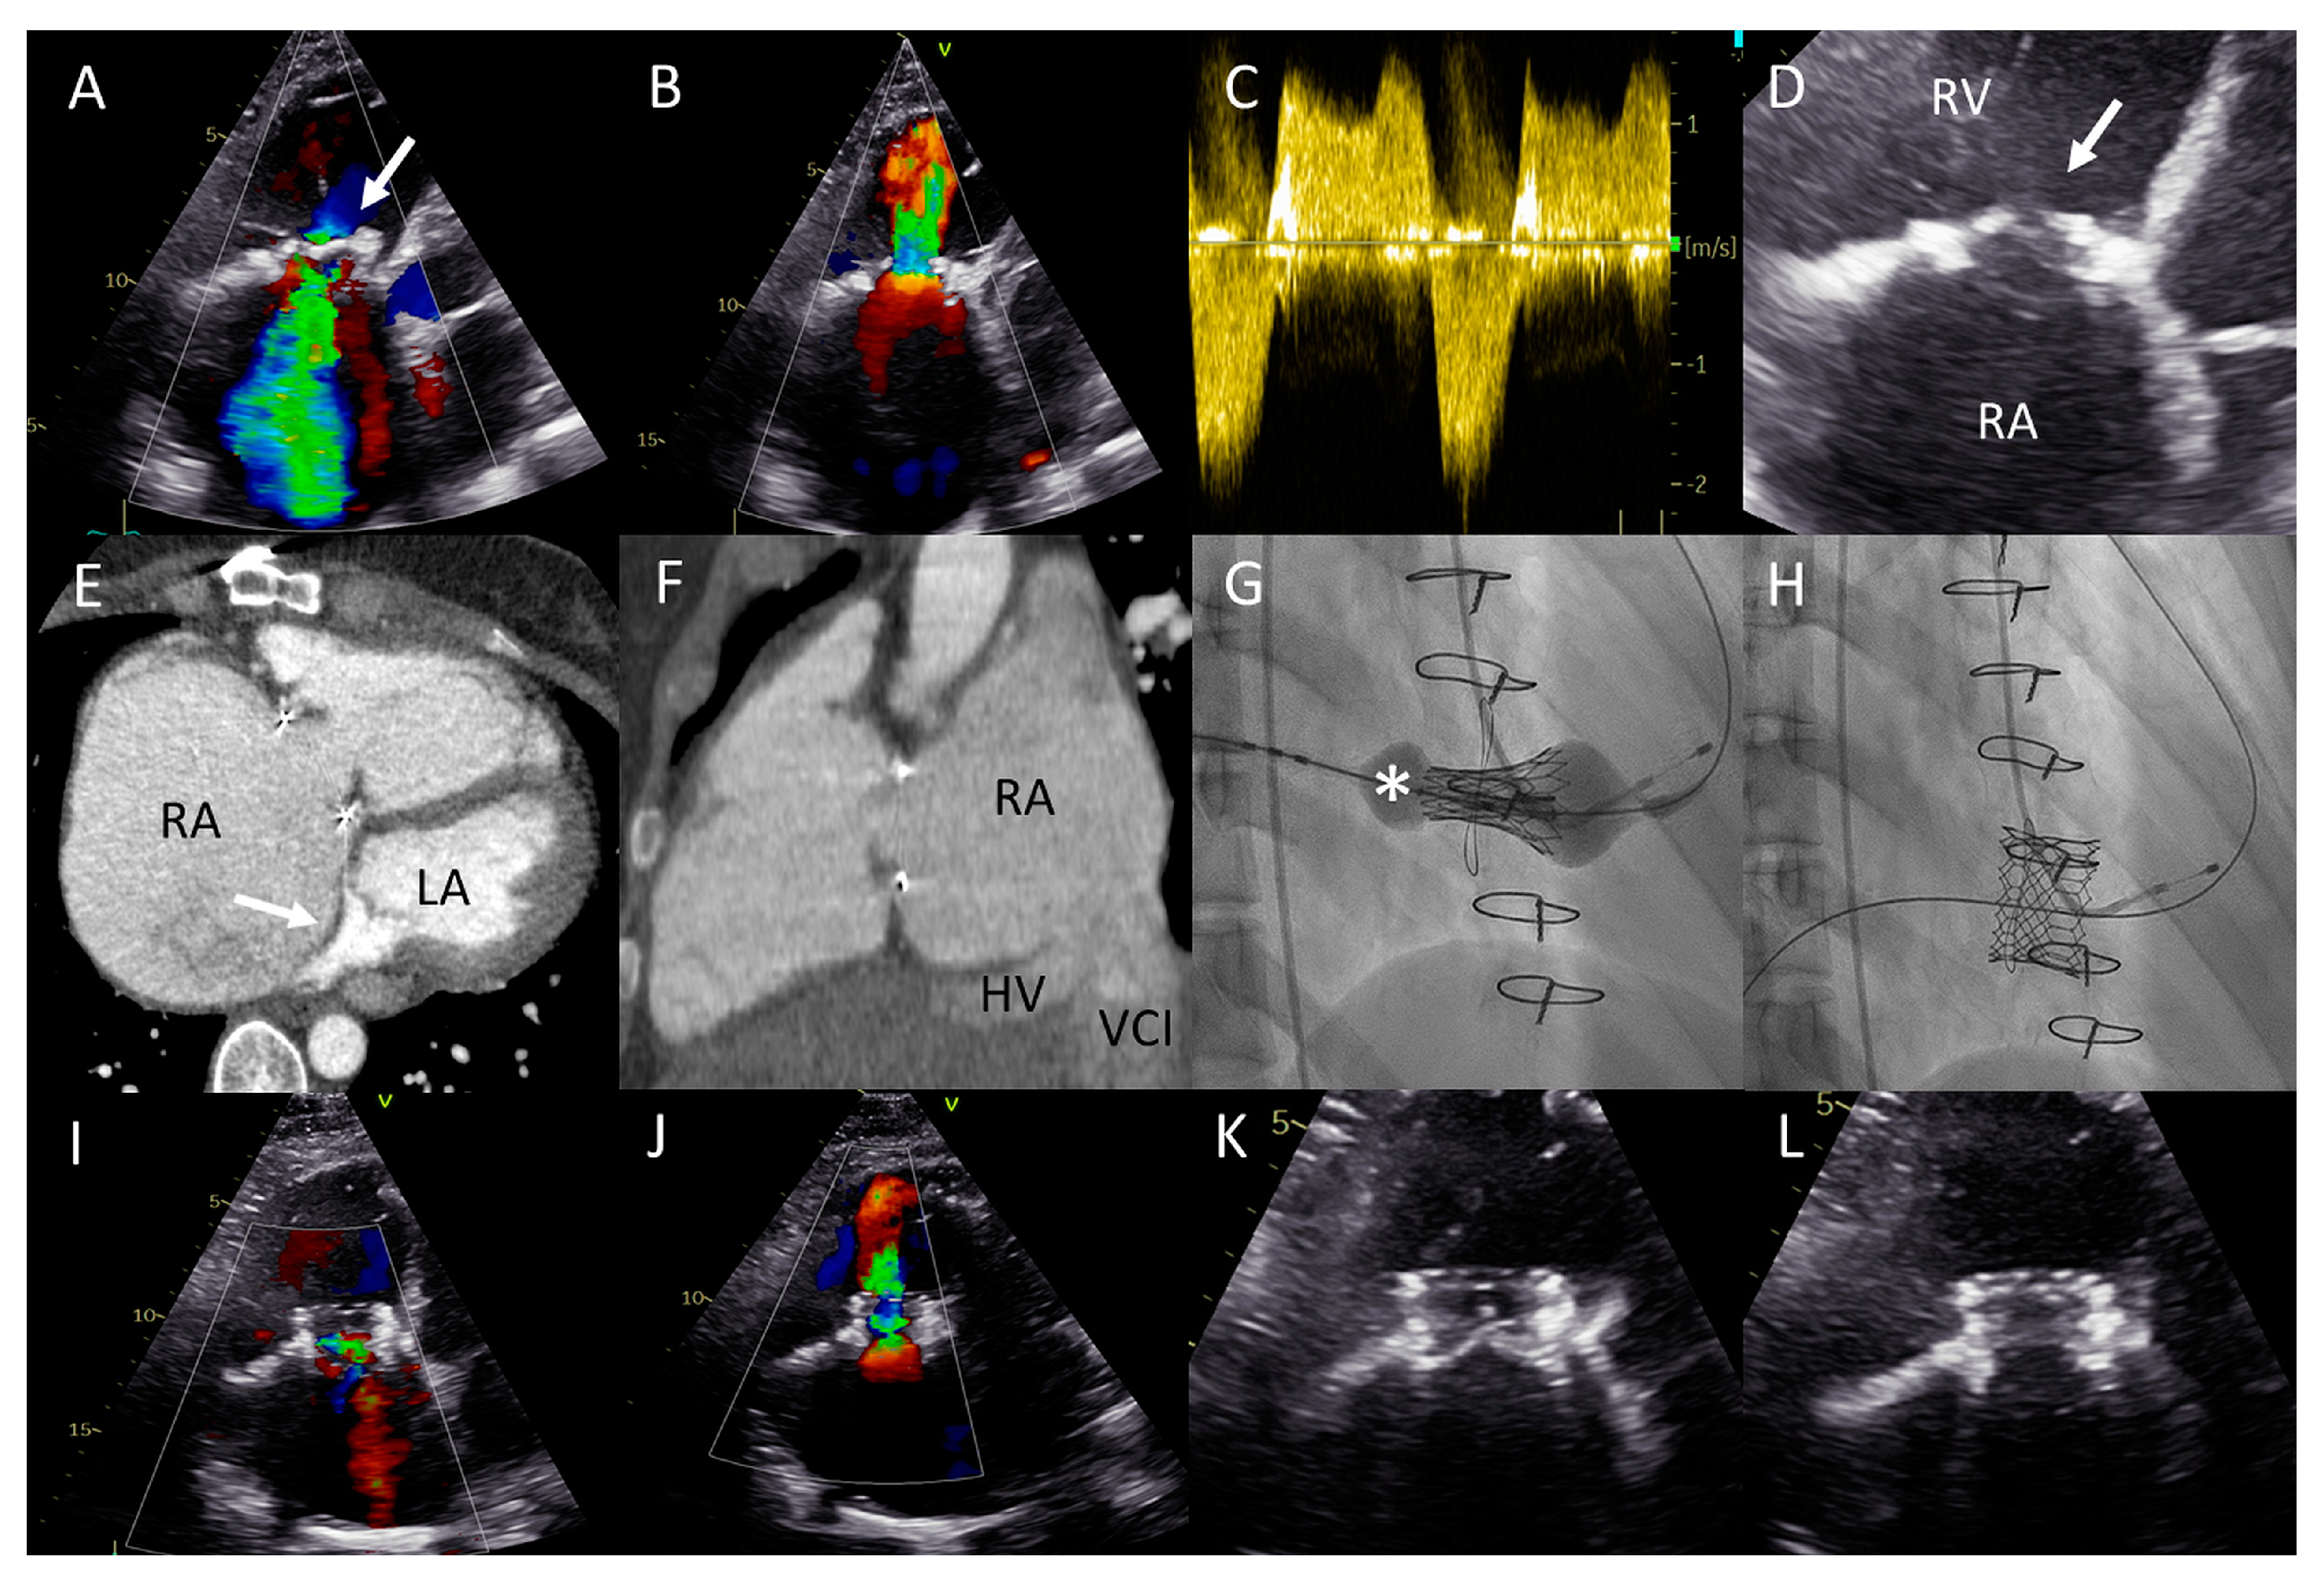

Figure 5.

(A) Distance between the right internal jugular vein and tricuspid valve (TV) measured on a computed tomography (CT) scan in a coronal plane (arrow). (B) Severely dilated mono-atrium (asterisk) on CT scan in a sagittal plane. (C) Implantation of the second XTW clip (note the first XTW clip already released) under transesophageal echocardiography (TEE) guidance. (D) Preprocedural TEE imaging of the torrential (IV+) TR. (E) Periprocedural TEE showing TR after placing the first XTW clip. (F) TEE showing the significant reduction in TR after placing the second XTW clip to grade I–II.

As a result of the severely dilated annulus and tethering, the coaptation gap was large, and simultaneous grasping of both leaflets was challenging. The TriClip system has the advanced option of independent leaflet grasping. First, the anterior leaflet (technically more challenging) was grasped and, subsequently, after minor device repositioning under TEE guidance, the septal leaflet was captured and the clip was released. The first clip was implanted near the commissure to narrow the coaptation gap so that the second clip could be implanted to treat the regurgitation (Figure 5C), which decreased to moderate (Figure 5E,F). Three weeks after the percutaneous procedure, at the outpatient clinic, the patient reported a decrease in orthopnea and exercise-induced dyspnea as the NYHA functional class was reduced from IV to III. At 17 months follow-up, the patient remained in NYHA functional class III. However, multiple heart-failure-related admissions occurred during follow-up (latest level of NT-proBNP was 8092 ng/L) and the patient developed atrial fibrillation (AF) which was treated with amiodarone.